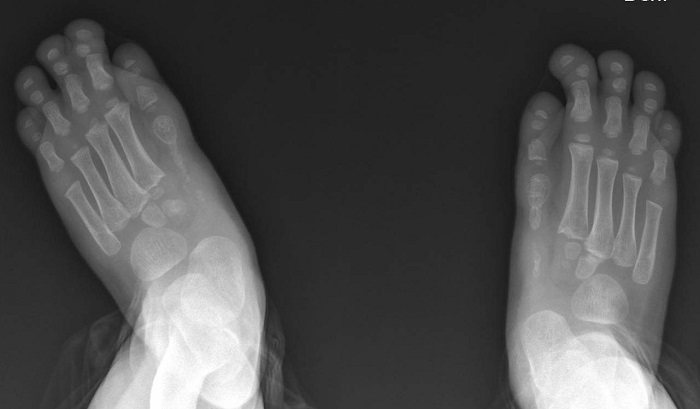

Niño de 3 años seguido desde el nacimiento en la consulta de Atención Primaria con rasgos dismórficos, como paladar ojival, hipertelorismo, retrognatia,  prominencia frontal y pies aductos con sindactilia y acortamiento de falanges en primer dedo de ambos pies (Figura 1).

Figura 1. Pies aductos con sindactilia y acortamiento de falanges en primer dedo de ambos pies